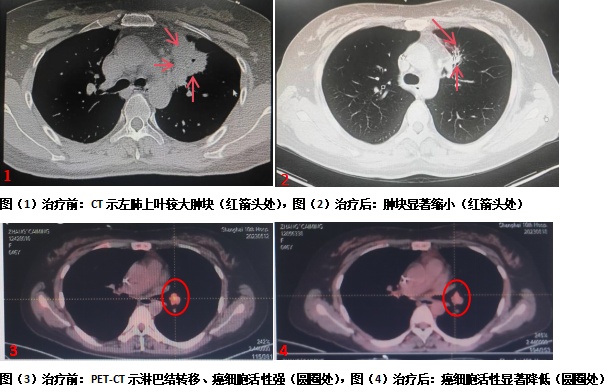

消融治疗在局麻下进行,在CT扫描定位及监测下,将冷冻治疗针精准穿刺置入瘤体,开启冷冻装置后,快速“冻死”了大块癌灶。整个消融治疗过程患者几乎无痛感,消融治疗顺利完成。

经过一年的治疗,张女士疗效显著,曾经的主要症状疼痛消失,日常生活几与健康人无异,同时PET-CT显示癌症原发灶被灭活,局部转移灶肺门淋巴结和远处转移病灶(髂骨转移)癌细胞活性明显被抑制,病灶显著缩小,整体癌症治疗获得了绝大部分缓解。绝境逢生,超乎想象的治疗效果也给张女士带来了信心,重燃了其对生活的希望。